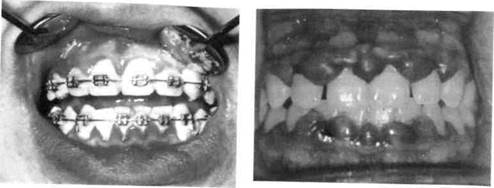

Хронический катаральный гингивит в стадии обострения характеризуется болевыми ощущениями, резкой спонтанной кровоточивостью десен. При этой форме воспаления десневого края часто отмечается поражение всех трех участков десны. Из анамнеза можно установить, что ребенок периодически страдал кровоточивостью десен и ранее (рис. 8.2; 8.3).

Рис. 8.2. Обострение хронического катарального гингивита при лечении несъемной ортодонтической техникой.

Рис. 8.3. Обострение хронического катарального гингивита.